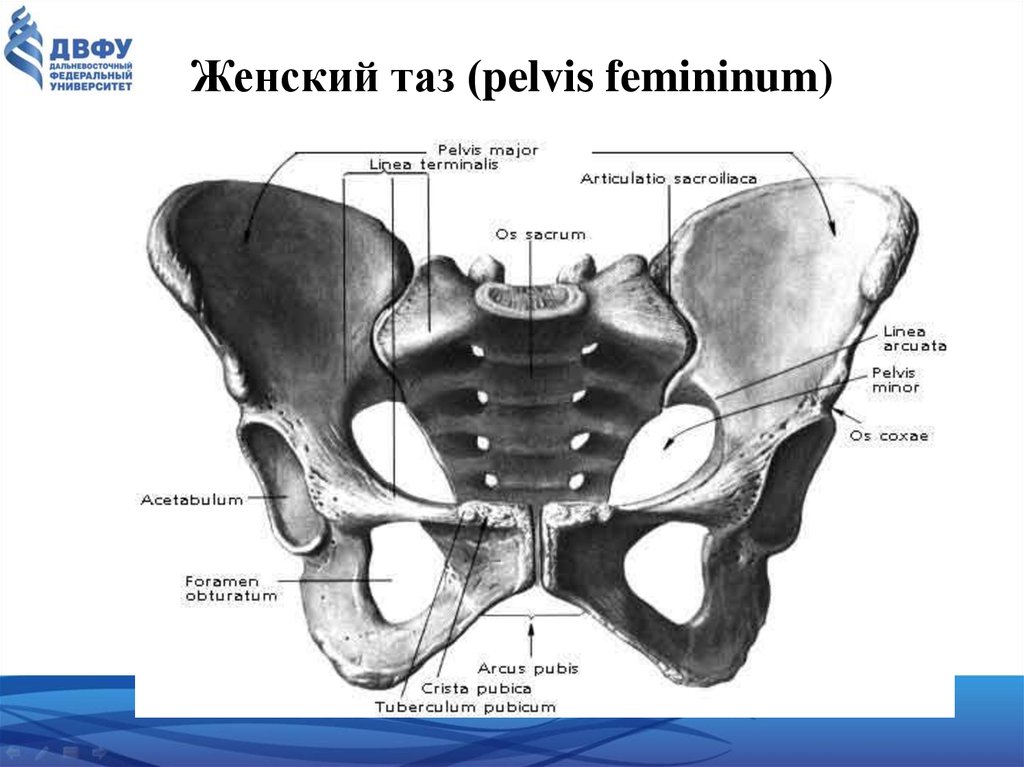

Анатомия малого таза: детальные схемы и изображения